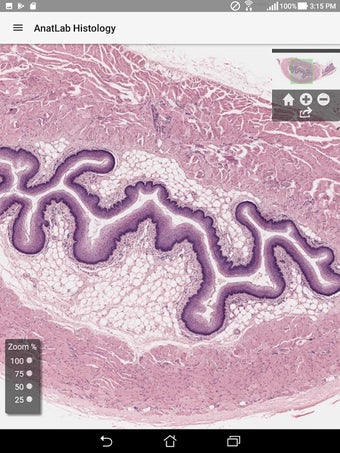

AnatLab Histology es una aplicación gratuita para Android desarrollada por Eolas Technologies Inc. que proporciona a los usuarios imágenes de diapositivas microscópicas de ultra alta resolución. Esta aplicación es una herramienta ideal para estudiantes, profesores, investigadores y el público en general. Con esta aplicación, pueden explorar el paisaje microscópico completo del cuerpo como si estuvieran mirando una colección de diapositivas reales en un microscopio físico. Tiene una función basada en la nube, la aplicación se puede acceder en cualquier dispositivo móvil Android, lo que la hace muy conveniente y accesible.

La aplicación ofrece una colección completa de imágenes de diapositivas microscópicas de histología que se pueden ver en ultra alta resolución. Las imágenes son de calidad excepcional y proporcionan una representación precisa del paisaje microscópico del cuerpo. La aplicación es fácil de usar y navegar, lo que permite a los usuarios explorar diferentes partes del cuerpo con facilidad.